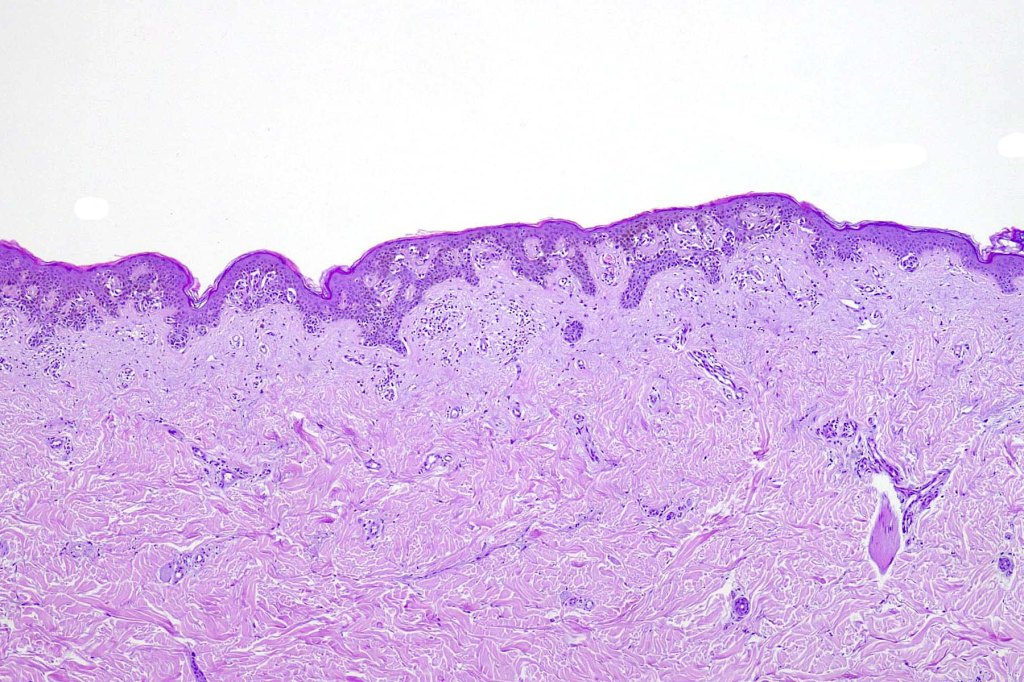

Histological features

- A broad lentiginous proliferation of atypical melanocytes unasscoiated with any loss of the rete ridges

7. Fibroplasia not seen and elastosis is either mild or absent